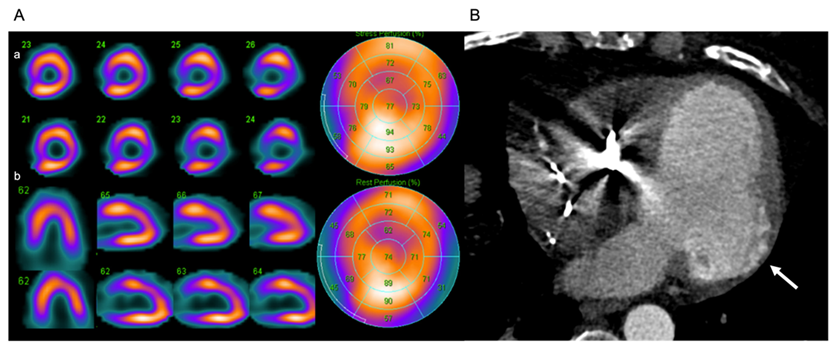

Nuclear medicine studies have found microvascular changes in the setting of chronic myocardial inflammation. The progression of left ventricular dysfunction is related to the extent and severity of myocardial perfusion abnormalities [68,69,70].

Clinical and experimental studies in murine models have demonstrated that individuals with CCC have abnormalities in microvascular perfusion regulation, microthrombi, and endothelial dysfunction [67,69,71]. The combination of these alterations could cause atypical chest pain; nevertheless, patients with confirmed CD may have angiographically normal coronary arteries, which provides an initial misdiagnosis [69,72,73,74].

6.5. Nuclear Cardiology

Nuclear cardiology perfusion studies can reveal reversible or non-reversible defects that simulate infarcts in regions of myocardial fibrosis [129]. The study of cardiac sympathetic denervation by nuclear cardiology has promising uses in the early identification of CD and risk stratification of ventricular arrhythmias, but the lack of standardized protocols limits its use [72,124,130].

Cardiac tomography may be an option in patients with contraindications (allergies to gadolinium contrast medium or ferromagnetic medical implants not compatible with the machine in use [131]) or unavailability of CMR [122,124] to characterize LVEF, coronary anatomy, myocardial perfusion defects, and ventricular aneurysms (Figure 9).